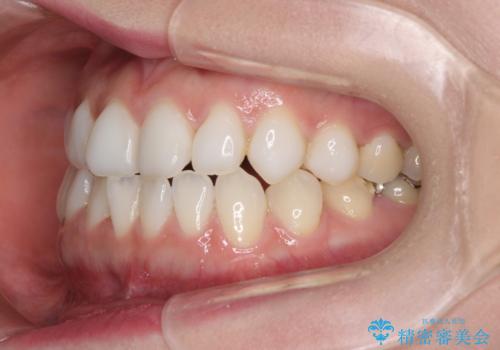

前歯のデコボコをすっきりと インビザライン矯正

- 前歯のデコボコを治したいとのことで来院された患者様です。

下顎が前方位にある方であったため、下顎の歯列全体の後方移動とIPR(歯と歯の間を削る)によってデコボコが解消するように設計し、インビザラインにより治療を行うこととしました。